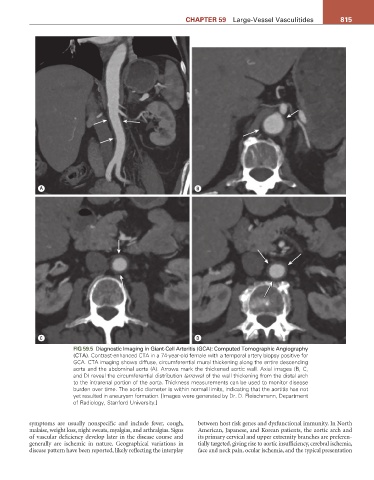

FIG 59.5 Diagnostic Imaging in Giant-Cell Arteritis (GCA): Computed Tomographic Angiography

(CTA). Contrast-enhanced CTA in a 74-year-old female with a temporal artery biopsy positive for

GCA. CTA imaging shows diffuse, circumferential mural thickening along the entire descending

aorta and the abdominal aorta (A). Arrows mark the thickened aortic wall. Axial images (B, C,

and D) reveal the circumferential distribution (arrows) of the wall thickening from the distal arch

to the intrarenal portion of the aorta. Thickness measurements can be used to monitor disease

burden over time. The aortic diameter is within normal limits, indicating that the aortitis has not

yet resulted in aneurysm formation. [Images were generated by Dr. D. Fleischmann, Department

of Radiology, Stanford University.]